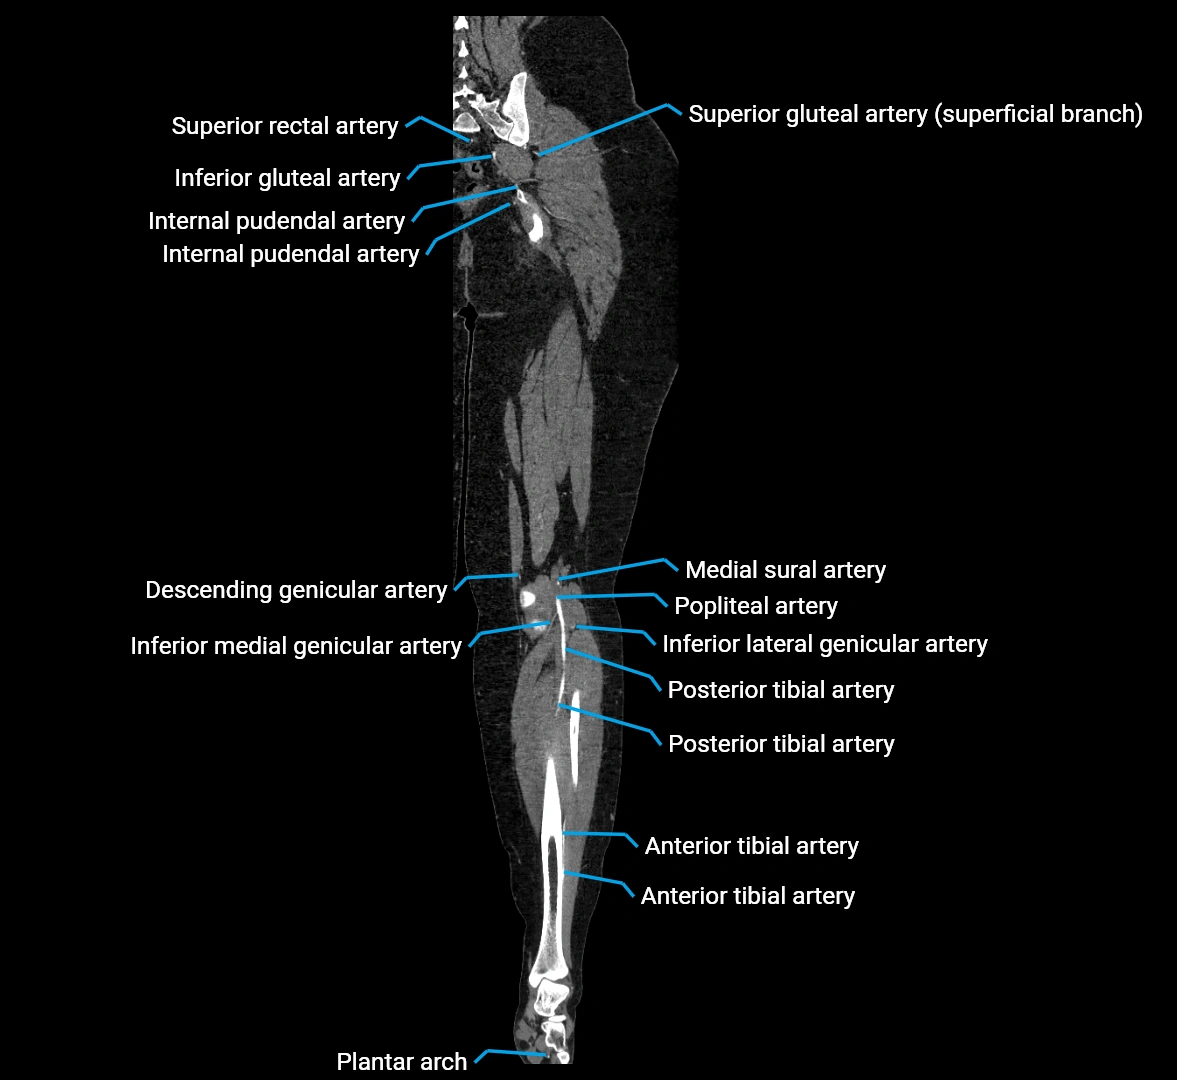

CT images

image

Contrast-enhanced CT (CTA):

• Gold standard for abdominal aortic imaging

• Provides excellent detail of lumen, wall, aneurysm, thrombus, and branch vessels

• Multiplanar and 3D reconstructions help in aneurysm measurement, stent graft planning, and dissection evaluation